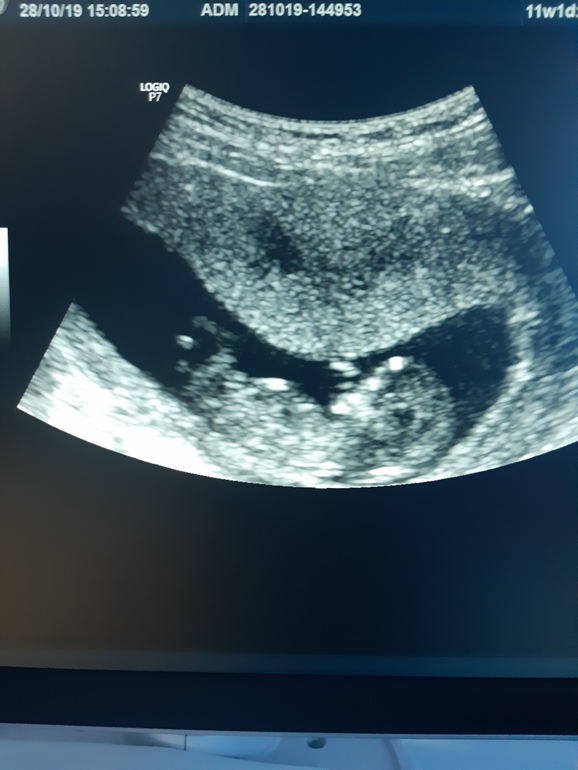

Узи в 12+1, пол не сказали, в ЖК , даже и ыото не дали, сама сыотала, посмотрите может есть опытные мне так любопытноооо

Девочка, если половой бугорок тот параллельный спинке белый отрезок. Мелкое изображение, его бы вуть крупнее. Впринципе у моей видно было в 12 также параллельно длинный отрезочек.